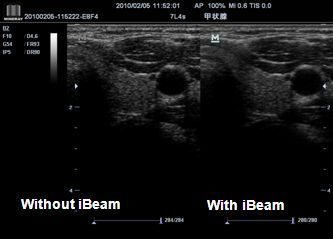

iBeam

С помощью этой функции можно соединить отдельные фрагменты, полученные под различными углами, в единое изображение, в результате чего достигается повышенное контрастное разрешение и улучшенная визуализация.